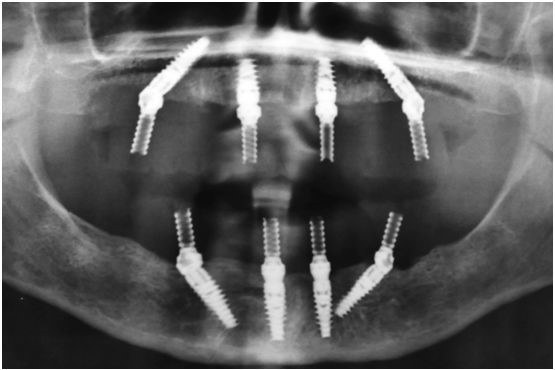

Исследование на рентгене после имплантации зубов

Раздел: Снимки-откровения